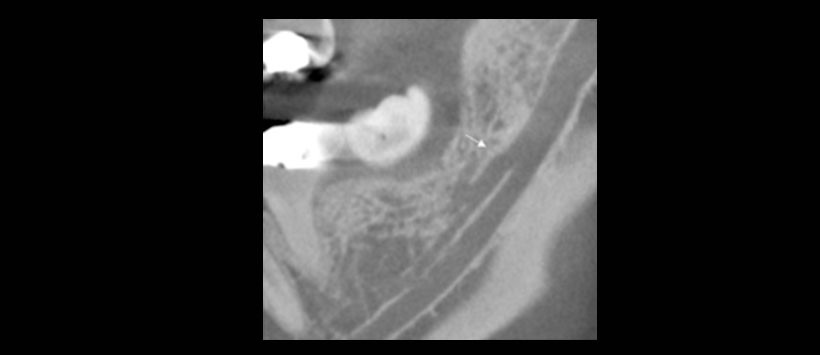

Tamaño: El tamaño se clasificó de acuerdo con el diámetro del canal de acceso. Un canal accesorio se consideraba grande si su diámetro era mayor o igual que el 50% del canal principal. Se consideró pequeño si era menos del 50%.

Figura 1: Medición del diámetro del conducto dentario inferior para clasificar al conducto accesorio en pequeño y grande.